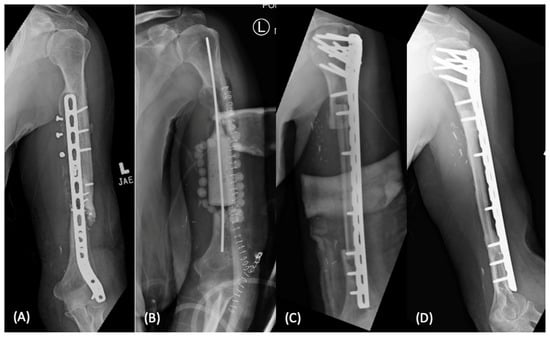

Figure 3.

Management of infected humeral shaft non-union with free vascularized fibula transfer (arrow) (A). Initially treated with removal of hardware, debridement, and temporary antibiotic cement spacer (B). Subsequently, the patient underwent vascularized free fibula transfer and revision open reduction internal fixation (C), with excellent graft incorporation at one-year follow up (D).